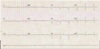

Interpret the tracing in A and B

- A) 1st degree AV block w/ non-conducted PAC

- B) 1st degree AV block w/ non-conducted PAC occurring in trigeminal rhythm